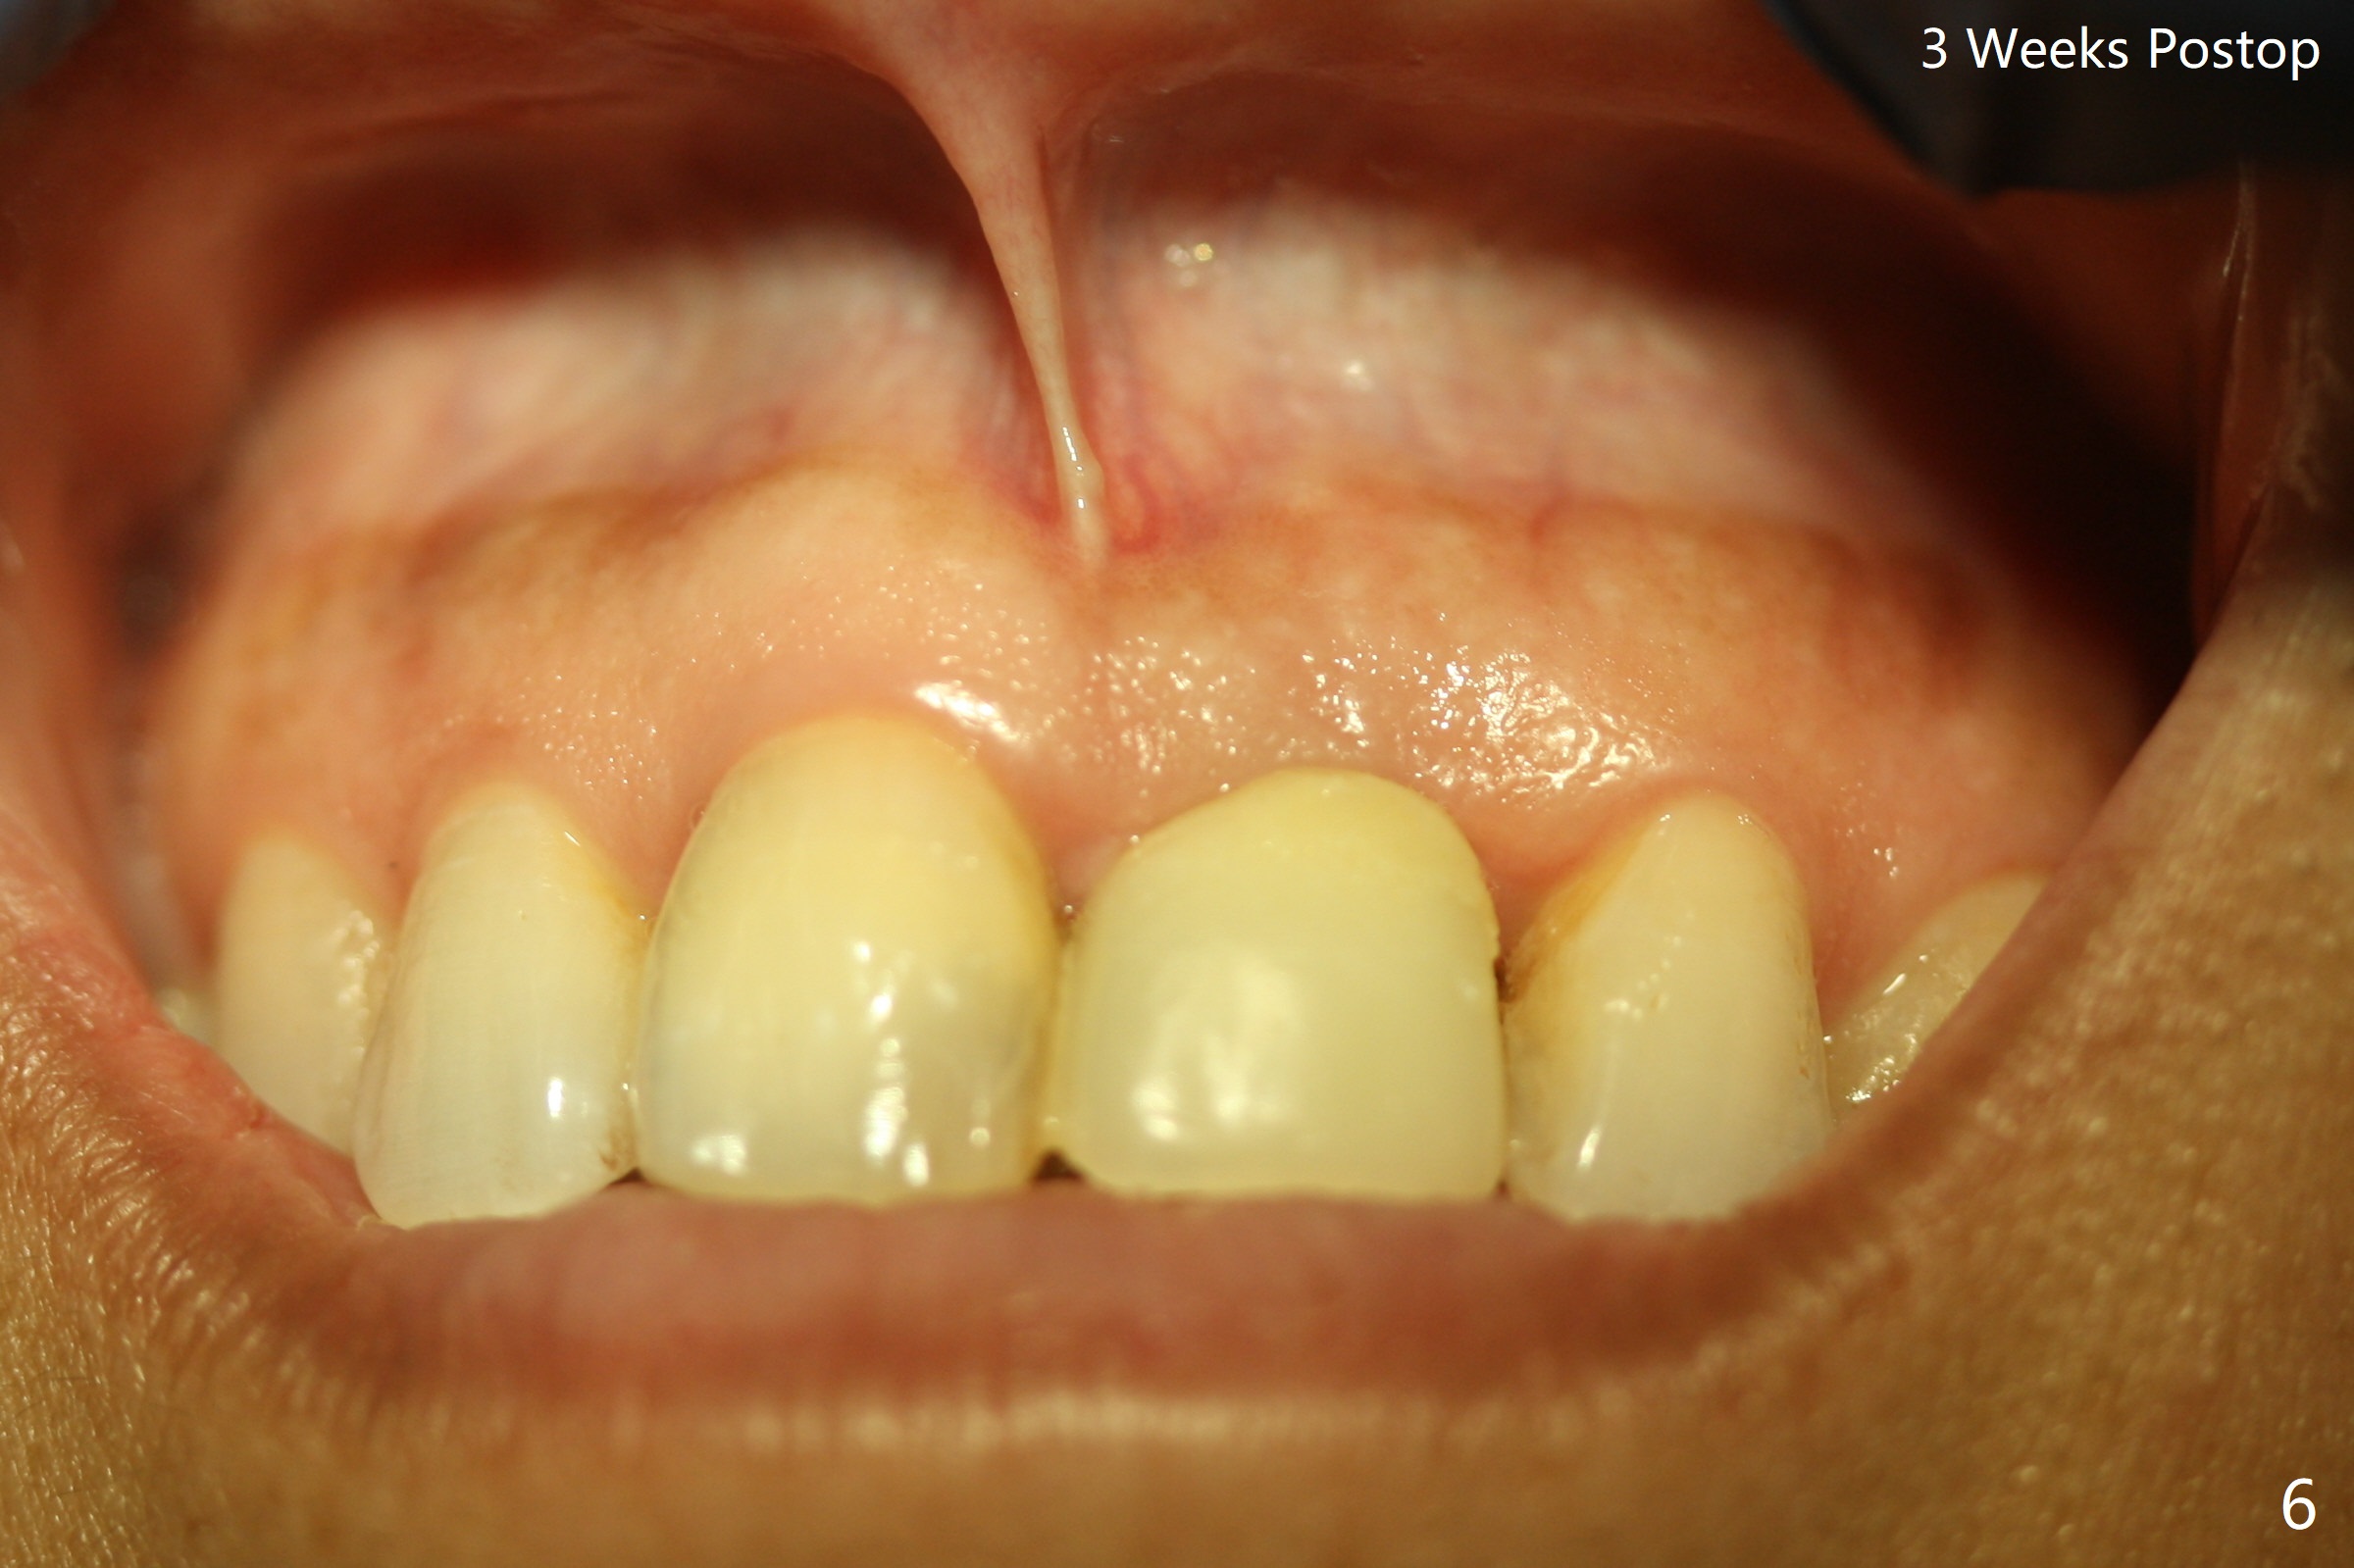

Except the depth, a 2.5x10 mm mini implant is placed with precision (in trajectory) at #9 (Fig.1-5). Confidence using surgical guide for the narrow ridge is enhanced due to placement of two digits against the buccal and palatal plates for tactile sensation. The depth issue is related to overprep with 2.2 mm drills. The torque is <15 Ncm. The immediate provisional is bonded to the neighboring teeth for retention. It appears that smaller drills should be made for guided surgery (such as 1.5 and 2.0 mm). The immediate provisional looks acceptable buccal and occlusal 3 weeks postop (Fig.6,7), although the palatal gingiva is erythematous (Fig.8, which is common after use of drill for access (tissue laceration), OHI offered). Three months postop (Fig.9), the palatal gingiva looks healthy (data not shown), while there is no bone loss around the implant (Fig.10). It remains the same 5 months postop (immediately post cementation, Fig.11) and 3,11 months post cementation (Fig.12,13). The labial gingiva is healthy (Fig.14), while the palatal one is less erythematous and edematous (Fig.15) than earlier (Fig.8).